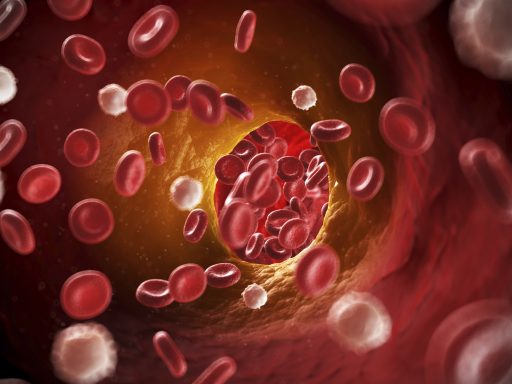

As part of our recent exhibition The Last Tsar: Blood and Revolution, rare disease expert, Dr Matthew Lumley, explains how the future is much brighter for people living with haemophilia today.